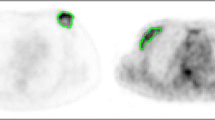

Texture analysis was performed using MaZda version 4.7 [32] on baseline and interim T2-weighted images. Post-contrast subtracted images from both examinations of each patient were considered side-by-side to identify maximum lesion diameter on each; subsequently these slices were matched to the appropriate slice on the T2 acquisition for region of interest (ROI) positioning on comparable slices (see Fig. 2). All image analysis was performed blinded to patient outcome, clinical and pathology information.

Region of interest (ROIs) (red) drawn for texture analysis on two patients, with slices matched between baseline (left column) and interim (right column) examinations. Insert images highlight lesion locations without ROI overlay. Image (a) and (b) are from slice-matched T2-weighted images from a woman who had a RCB-III at final pathology, while (c) and (d) are from slice-matched images in a patient that ultimately achieved a pCR at end of treatment. Images (e) and (f) highlight the importance of correlation with the subtracted dynamic contrast-enhanced imaging (DCE) images, particularly in the case of non-mass enhancement, as shown

T2-weighted images were magnified to visualise the tumour border and an ROI drawn around the entire tumour on the imaging slice demonstrating maximum lesion diameter, with no marker clip present. Histograms were visualised to ensure no fat was erroneously present within the ROI (see Fig. 2). A 10 × 10 pixel ROI was placed in healthy, normal contralateral breast parenchyma to exclude systematic inter-scan differences (as shown in Fig. 2(c,d)). These were placed in comparable regions of breast parenchyma at baseline and interim to ensure consistency and care was taken to exclude presence of vessels within the ROI. Data was rescaled to 6 bits/pixel and the image histogram normalized to within 3 standard deviations of the mean to minimise brightness and contrast variations. Entropy features, representing heterogeneity, were derived from the grey-level co-occurrence matrix [33], as these are reported in the literature as most appropriate for cancer imaging [29]. Inter-pixel distances of n = 2 and n = 5 were calculated to depict fine and coarse texture. Raw feature values were exported for statistical analysis.